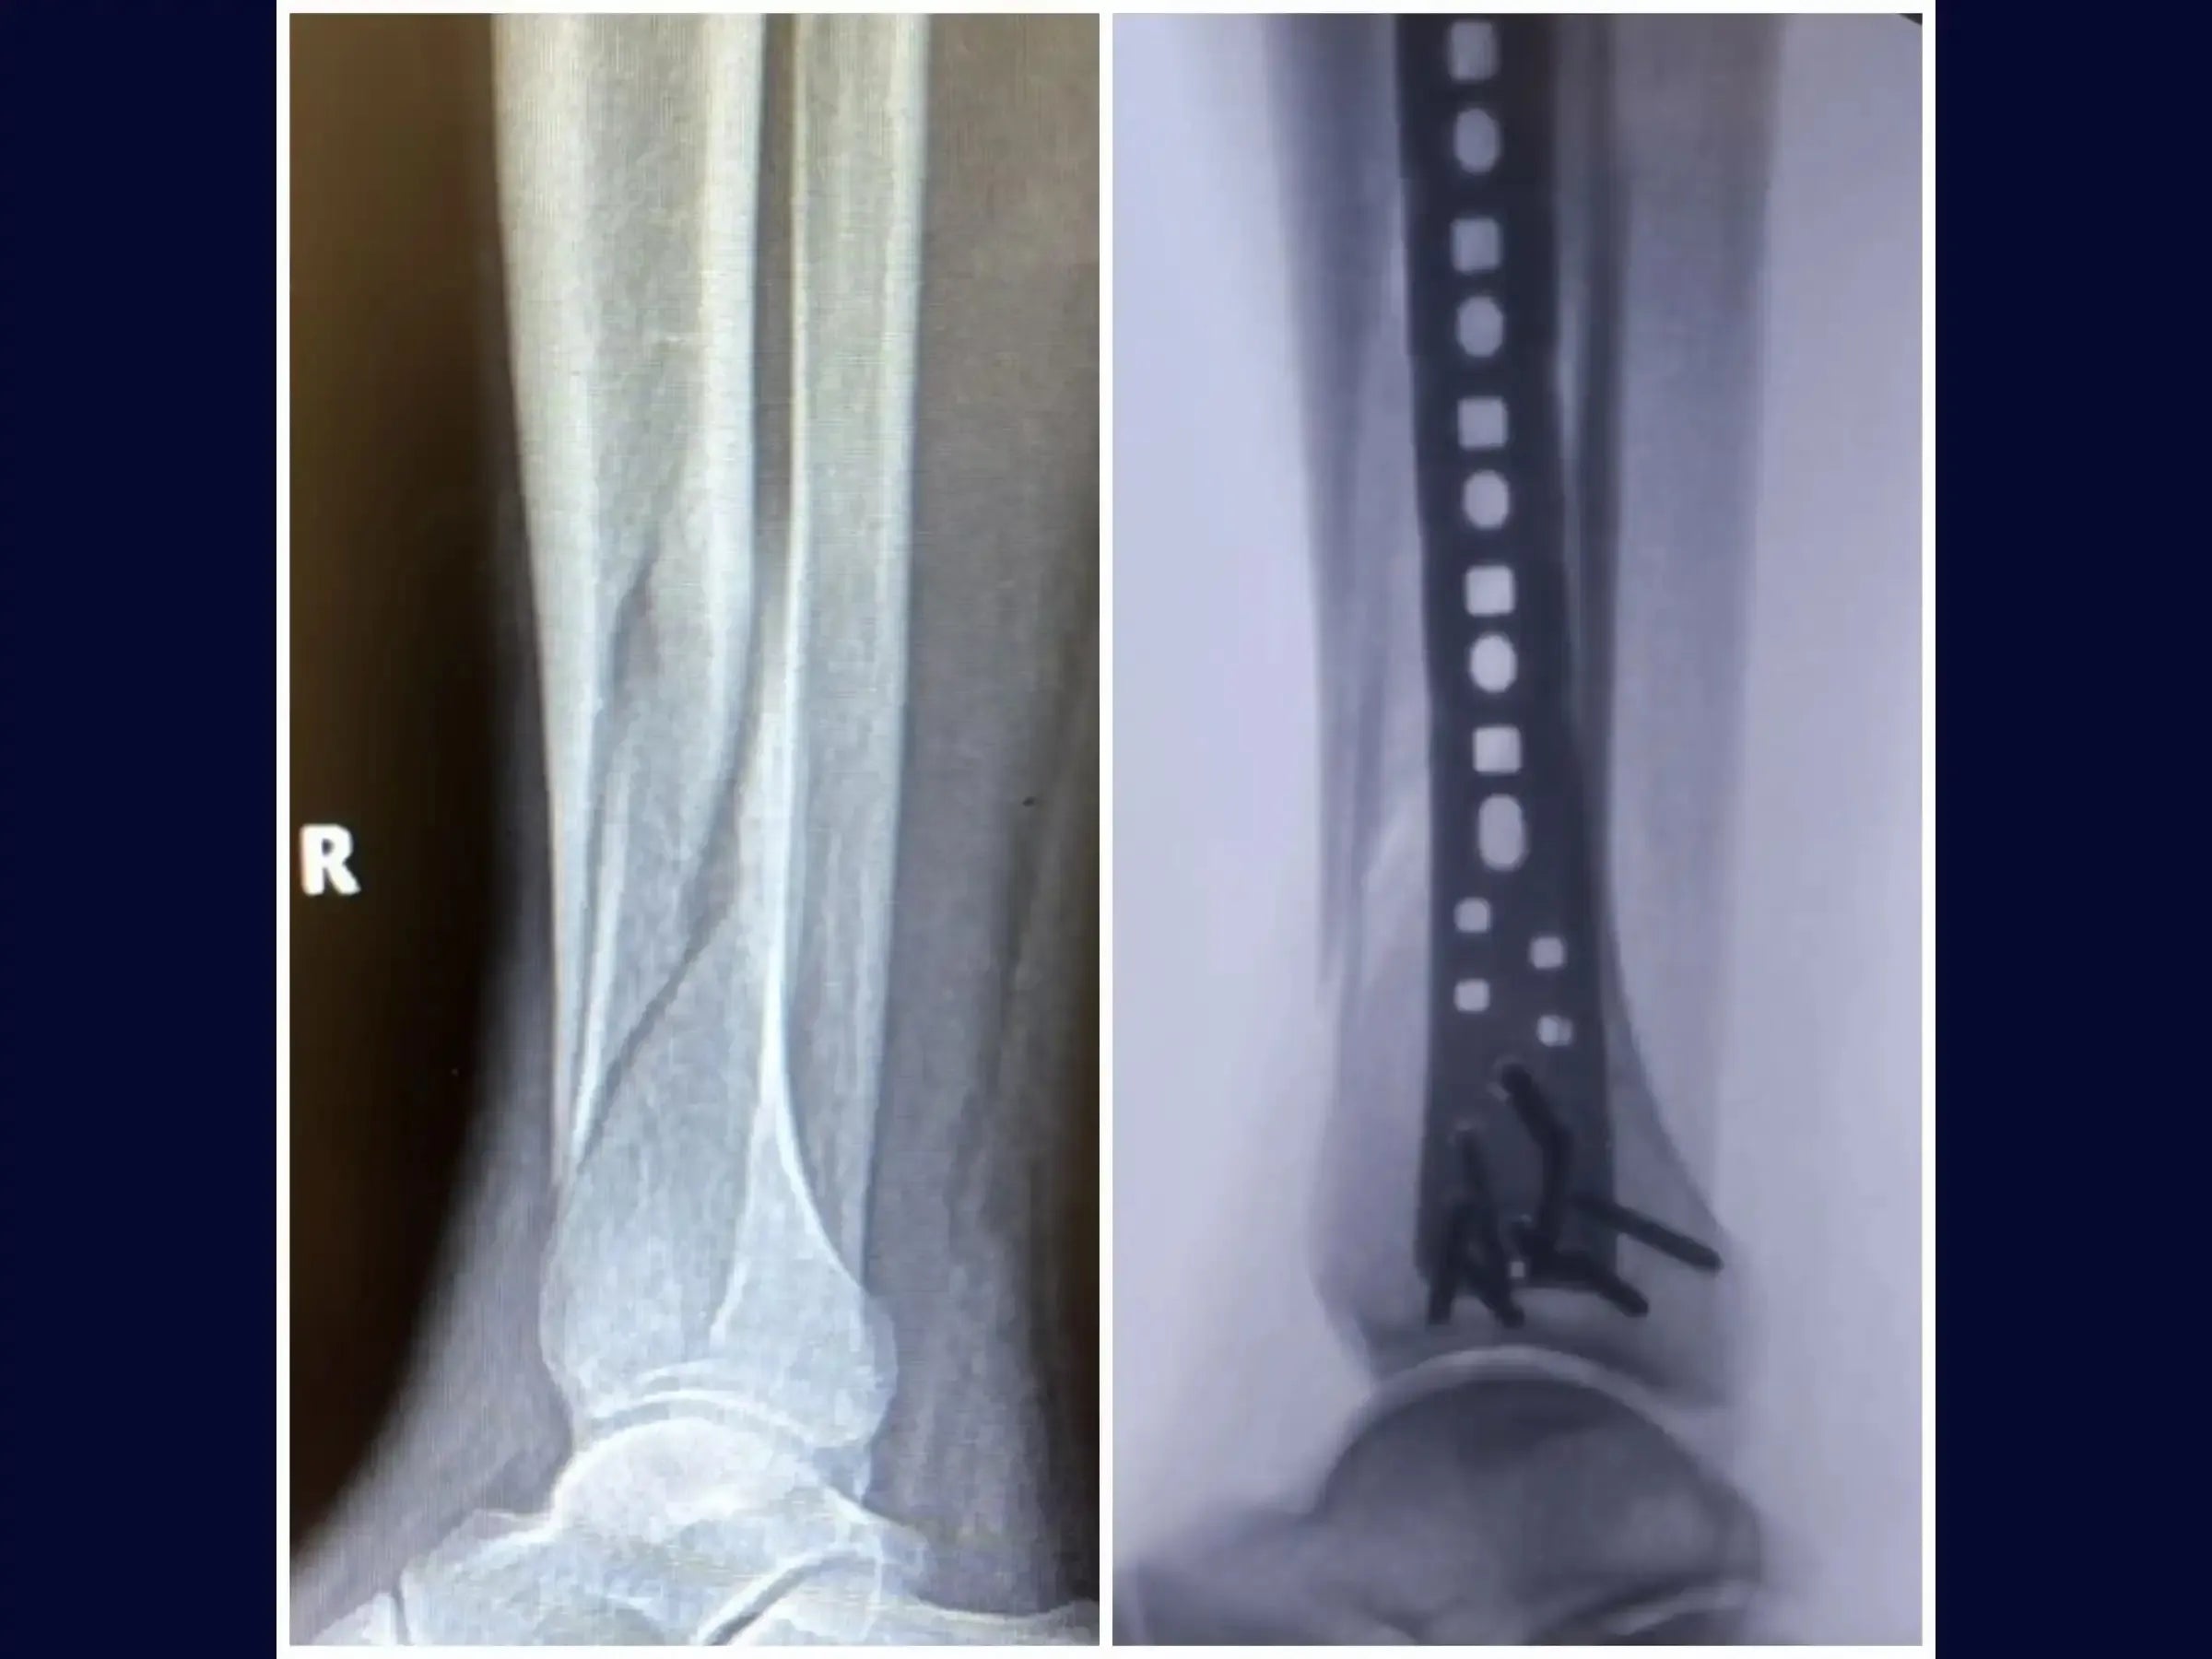

- Surgical treatment of diaphyseal tibial fractures with long oblique and spiral patterns.

- Tunnel Creation and Plate Insertion: Technique for creating a submuscular tunnel with a long dissector, guided by palpation, for the introduction of the anatomically pre-twisted locked plate.

- Definitive Fixation and Optimization of Osteosynthesis: Procedure for drilling and inserting distal screws in the distal third of the tibia, with the plate positioned snugly against the bone to avoid irritation of the medial malleolus.Insertion of an additional screw near the fracture focus to optimize energy distribution and balance the osteosynthesis. Finalization with proximal screws.

- Comprehensive Final Assessment: Confirmation of anatomical reduction, sufficient number of screws, proper positioning of the long plate, relative stability, and maintenance of external rotation similar to the contralateral side.